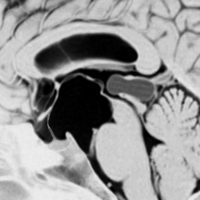

20年間経過観察されている松果体のう胞です。ガドリニウム増強で周囲が白く増強されているのですが,これはのう胞壁ではなく静脈です。

松果体のう胞の経過観察にはガドリニウム増強する必要はないし,そもそも中濃水道橋策がないものでは数年もみれば十分なものです。